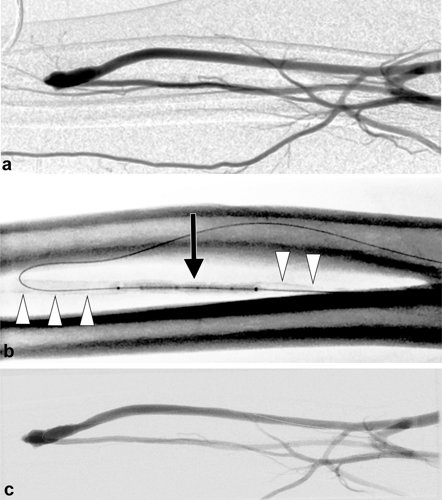

Figure 1 (a) Brachial artery angiogram of the functionally immature radiocephalic fistula. The distal radial artery was not well opacified due to preferential flow into the fistula. (b) Spot radiograph during the intravascular lithotripsy showed the balloon (arrow) inflated in the radial artery during treatment. Lithotripsy was performed throughout the inflow radial artery. Medial calcinosis was evident throughout the radial artery (white arrowheads). (c) Completion angiogram after lithotripsy of the entire radial artery inflow showed increased flow and washout of the radial artery and fistula.

Source: JVIR